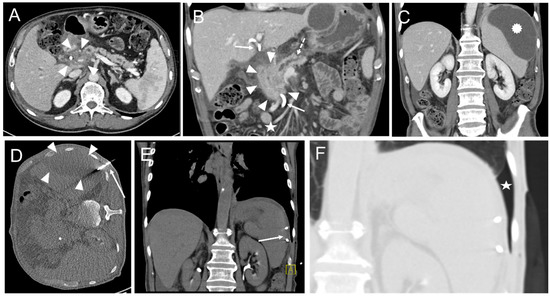

In one intervention, an instant replacement was necessary due to the dislocation of the initial drainage. In one case fluid collection was too small for drainage placement. Complications occurring during or immediately after the intervention were seen in three patients (1.8%). These comprised one major complication (according to SIR criteria) where operative revision was necessary (Table 4, Figure 3 and Figure 4).

Figure 4. CT-guided drainage placement with a subsequent major complication according to SIR. (A) 71-year-old male underwent pancreaticoduodenectomy (PD) due to ductal pancreatic adenocarcinoma. Sixteen days later abdominal revision surgery with hematoma evacuation was performed due to arterial hemorrhage from the hepatic artery and small bowel segment resection due to adhesion ileus. Twenty-seven days after PD a perihepatic subcapsular fluid collection was diagnosed on a CT scan, mainly located at the ventrolateral and medial margins (arrowheads). (B) CT fluoroscopy-guided placement of a 10F Flexima® single lumen drainage (arrow; Boston Scientific, Marlborough, MA, USA) within the fluid collection (arrowheads). After placement, a significant reduction of the fluid was observed. (C) Contrast-enhanced CT control scan after eleven days revealed an increase of the subcapsular fluid collections mainly next to the right liver lobe (arrowheads). Contrast medium extravasation occurred inferior to the left liver lobe (segment 3) from the left gastric artery in terms of active bleeding from this vessel. Contrast medium extravasation could also be found in the fluid collection (open arrowheads). Arrow: drainage. An angiographic examination (not shown) performed immediately thereafter did not provide the source of the bleeding. (D) Repeated angiography after another 6 days showed extravasation of the contrast agent (arrowheads) from the left hepatic artery (arrow). (E) Superselective embolization of the bleeding was performed by placement of an 18/4 (Cook Medical, Bloomington, Indiana, USA) Tornado® microcoil in the vessel (arrow) supplying the hemorrhage. However, there was an initial misplacement of the coil (dashed arrow), which came to rest in the adjacent pseudoaneurysm (arrowheads). (F) Subsequently, placement of a second 18/4 Tornado® coil was conducted in the vessel neck (arrow; initially misplaced coil: dashed arrow). (G) The final angiographic control did not show a remaining contrast agent extravasation. Arrow: Vessel neck with coil; arrowheads: hematoma; dashed arrow: initially misplaced coil. In conjunction with the clinical course, the case was considered to be an arrosion hemorrhage induced by the drainage placement in combination with insufficiency of the biliodigestive anastomosis.